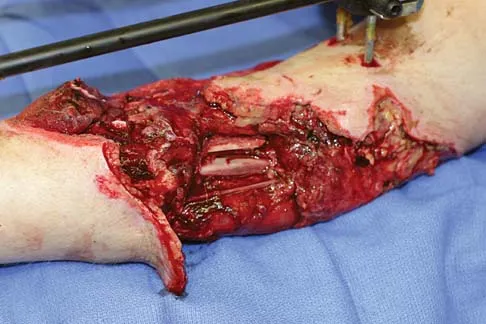

Question 79

A healthy 25-year-old man sustains a grade IIIB open tibial fracture. Following appropriate debridement, irrigation, and stabilization with an external fixator, the soft-tissue injury is shown in Figure 30. What is the most appropriate definitive soft-tissue coverage procedure?

Explanation